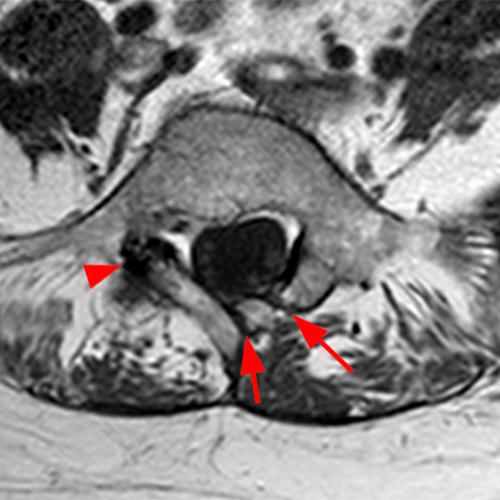

Case 2: T1-weighted (4A) and T2-weighted (4B) axial images show T1 hypointensity and T2 hyperintensity (arrowheads) in the left lamina of L5 adjacent to a small hypointense line (arrows) which traverses the lamina.

Case 2: Acute left-sided laminolysis